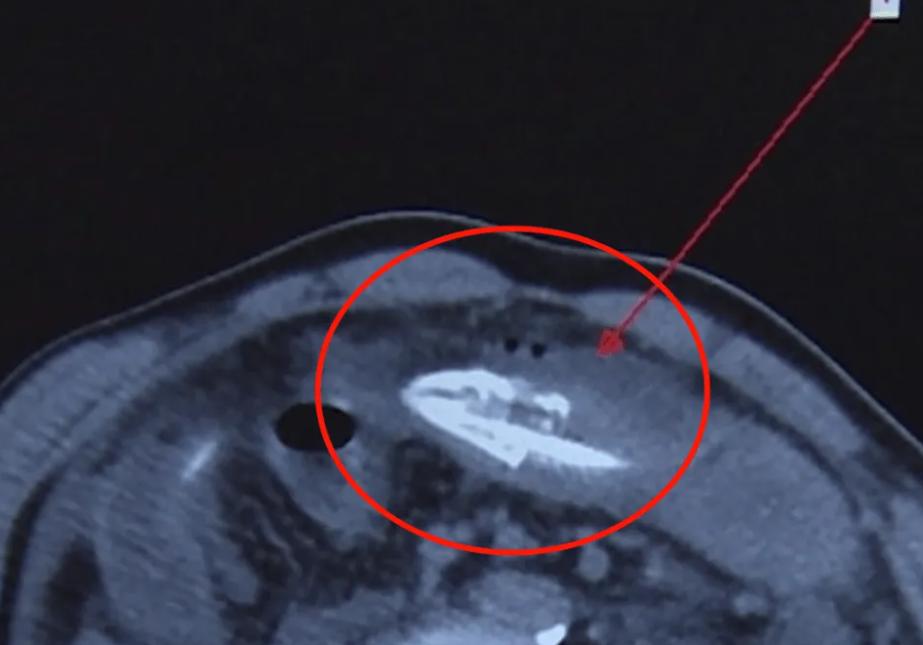

2021年江苏一男子,因为黄鳝钻入肚中,疼痛难忍急忙就医。经过医院检查,黄鳝从头到尾,位于结肠肝区,到乙状结肠之间,其长度很可能达到了40公分左右, 这么一个大家伙,究竟是这么跑到肚子里的?

转而开始说出解决方法,因为暂时还不能确定黄鳝,在人体内是否存活,所以建议选择全麻手术,通过剖腹的方式,将黄鳝取出,疼痛难忍的男子,急忙点头答应,一段时间过后,医生手术成功,黄鳝被取出。

取出的黄鳝,体长有20厘米左右,已经死亡 ,但因为黄鳝死亡时的挣扎,让男子的大肠因为黄鳝的破坏,受到了一定的损伤,为了防止伤口感染,而患上溶血症等问题,医生又对男子的大肠进行了一番处理。